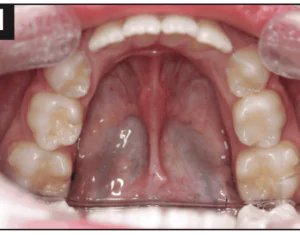

We all need something from which to base our actions, and we need to believe that our actions are appropriate for our patients. Occlusion is